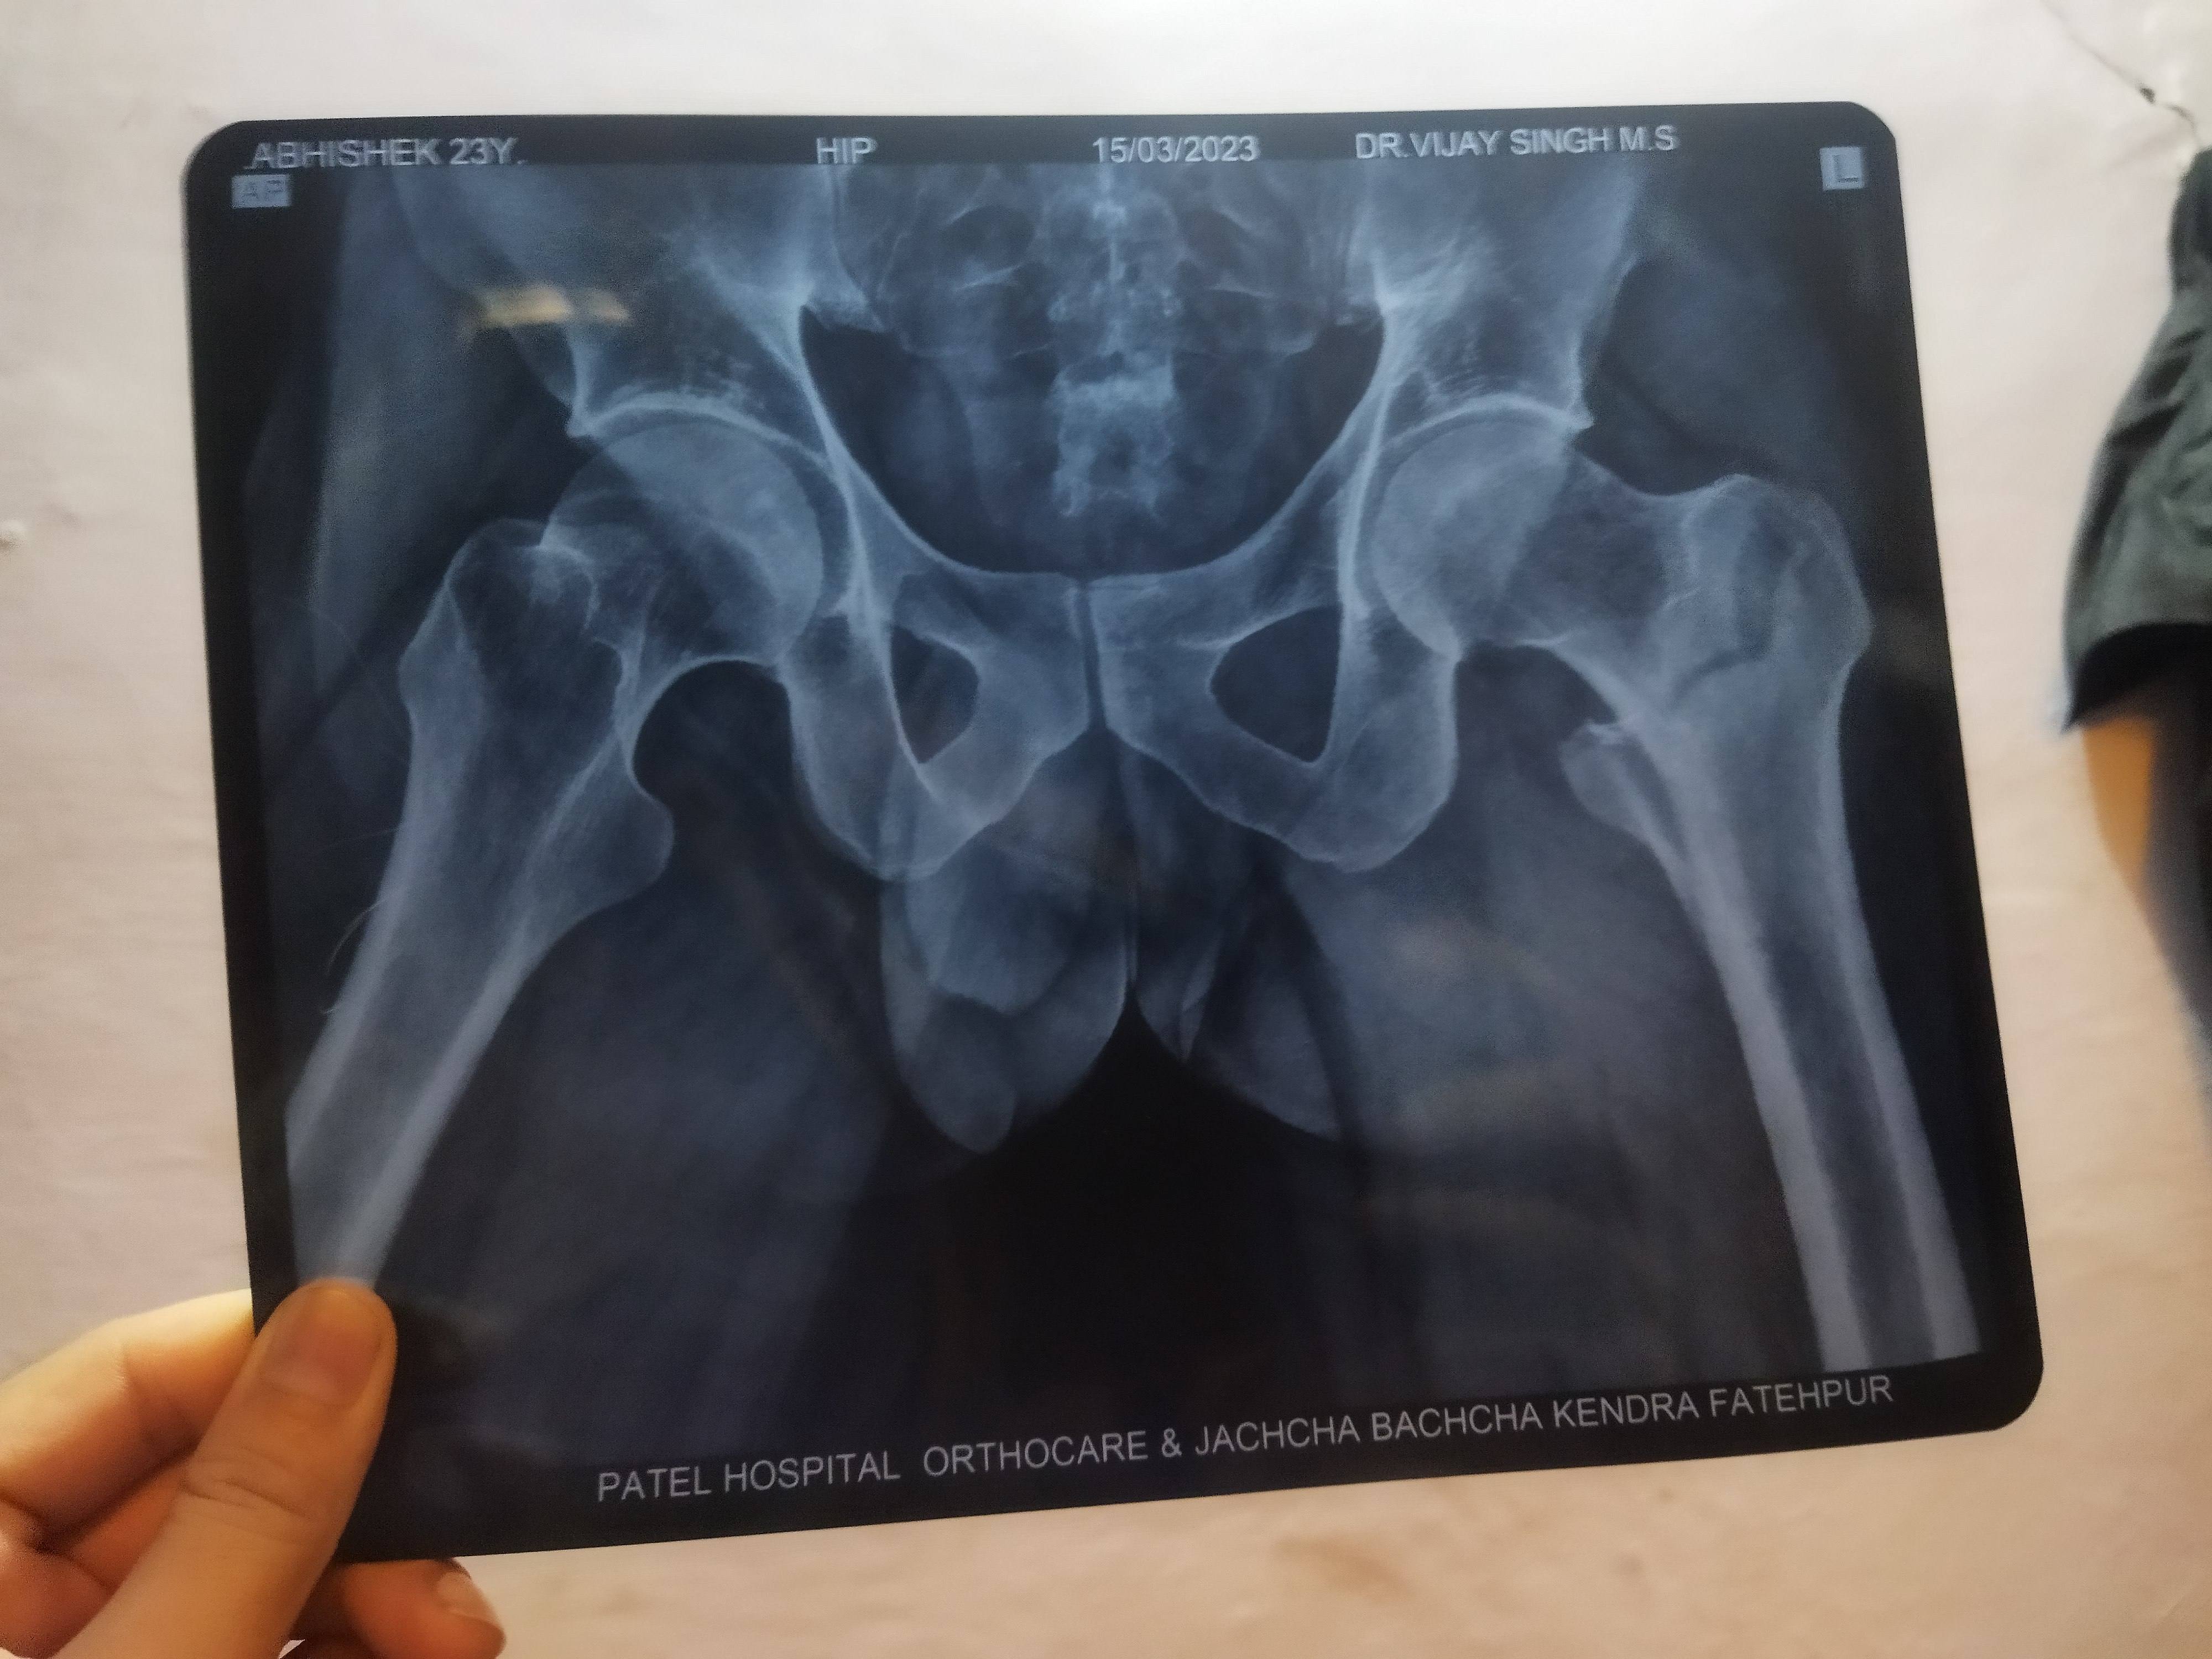

Abhi Singh

. Following